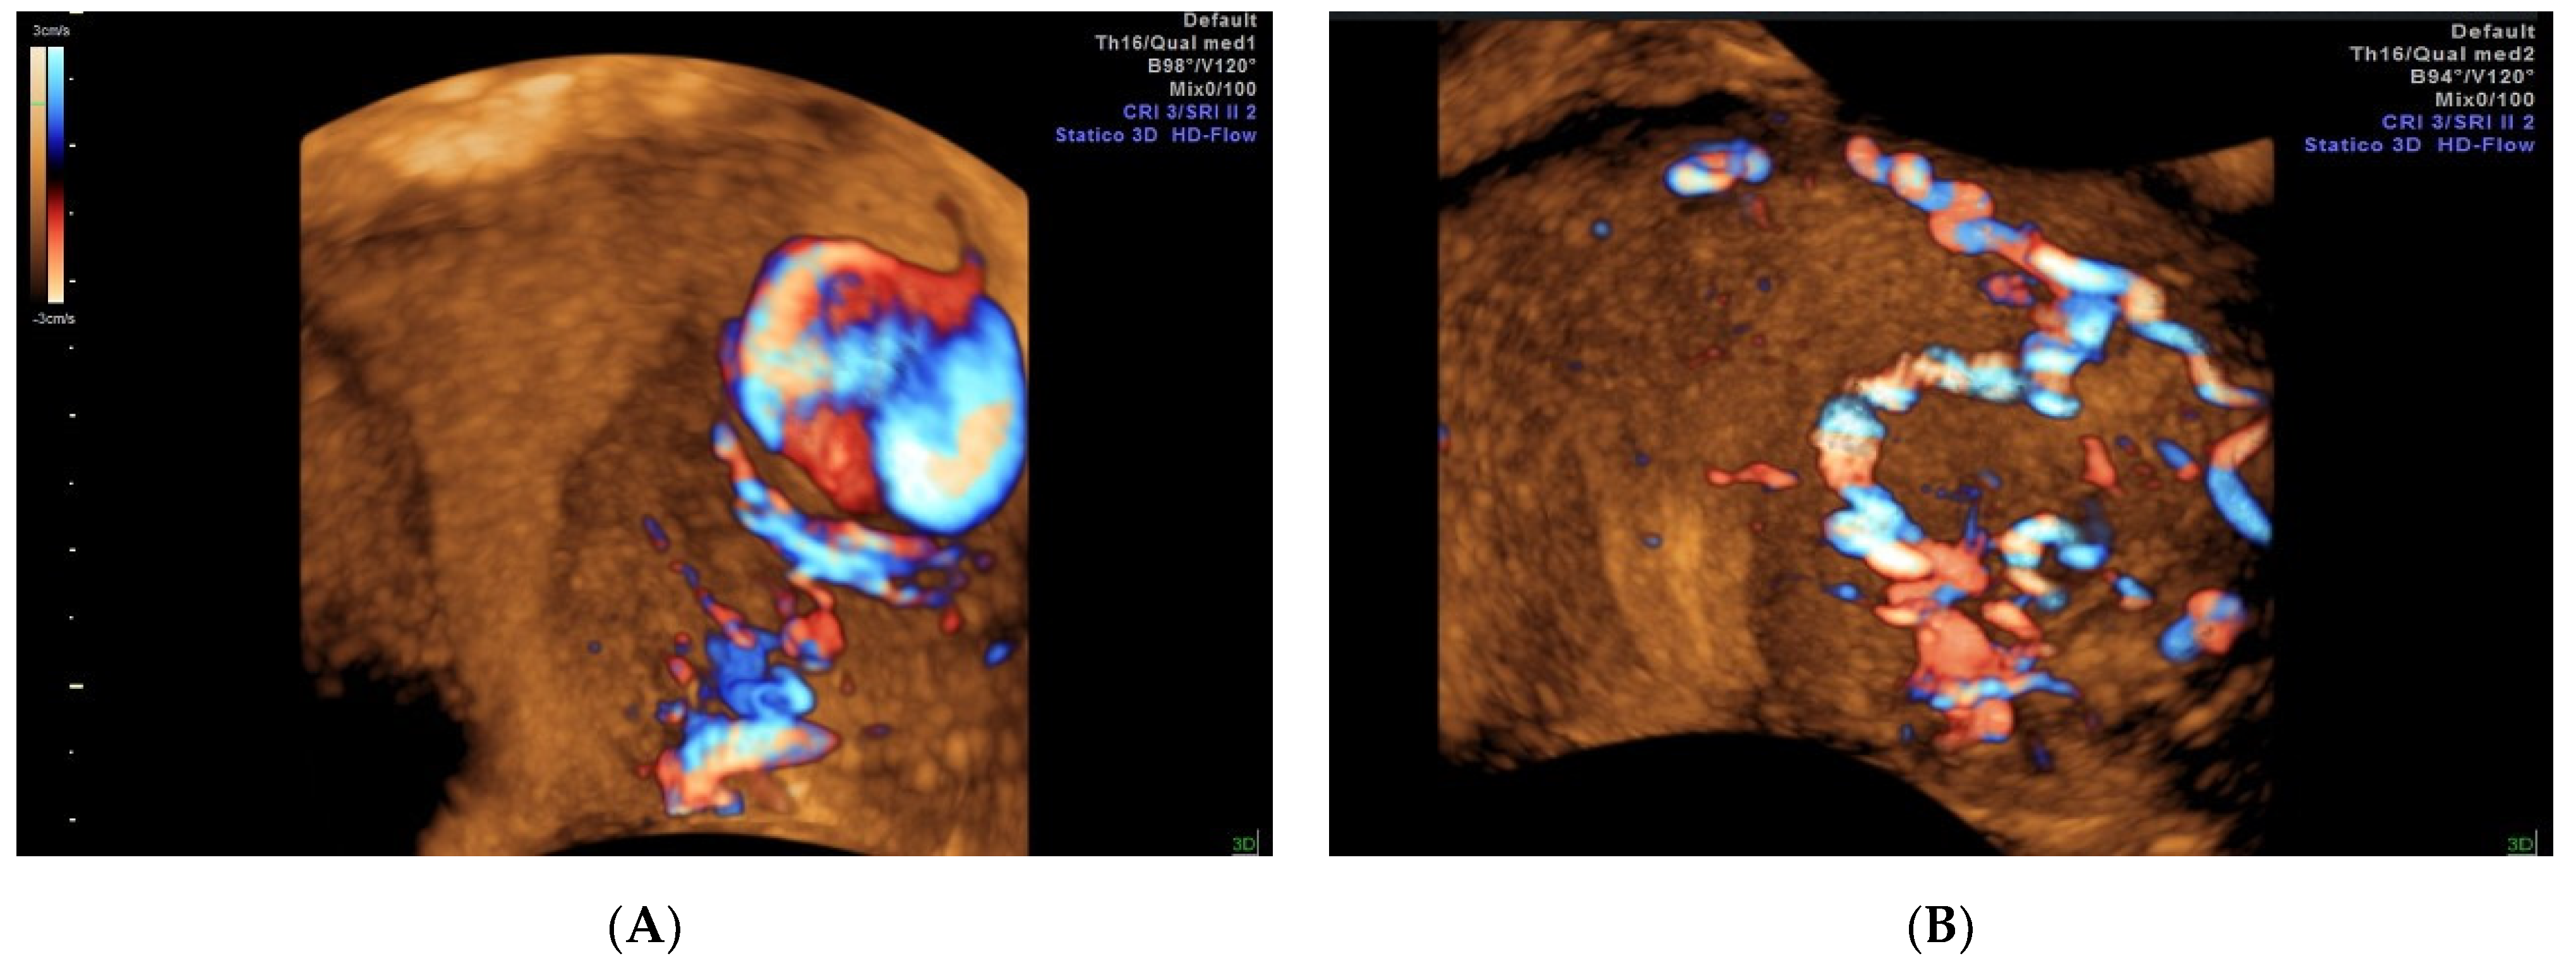

2. Case Report